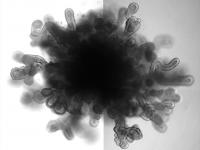

Bright-field images of day 50 LBO-derived Matrigel colonies from RUES2 cells. Representative of six independent experiments. Scale bars, 500?μm.

Snoeck lab/Columbia University Medical Center